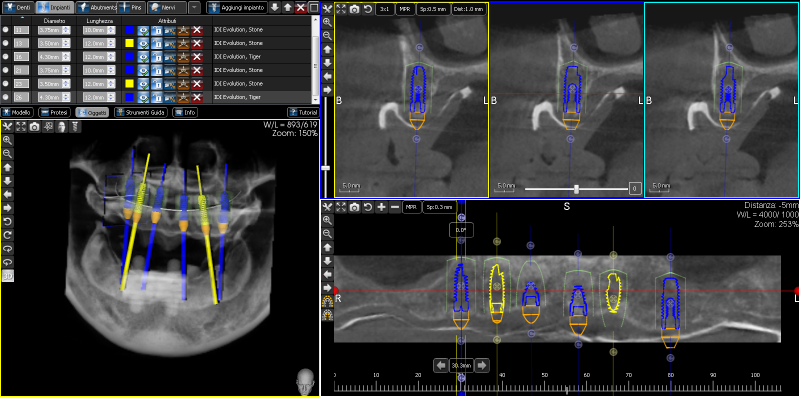

Chirurgia guidata

Attraverso la chirurgia guidata vengono realizzati impianti e forature chirurgiche in modo digitale ottenendo risultati altamente accurati, sicuri e prevedibili, direttamente il laboratorio.